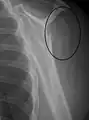

Proximal humerus fracture